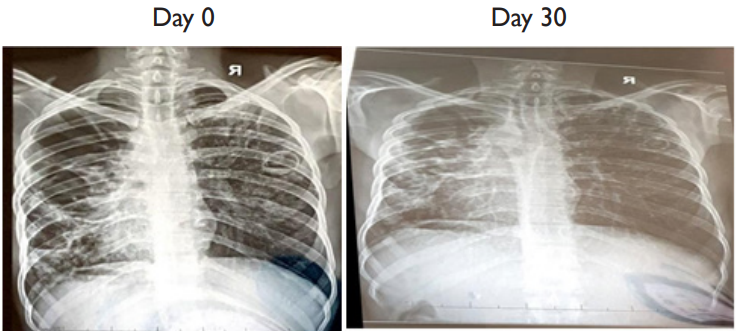

One patient however deserves a particular attention. Patient no 032 IK HA 03.22 was admitted at Heal Africa Hospital on March 13, 2022, with the following symptoms: persistent diurnal and nocturnal cough, asthenia, aphonia, extreme weight loss and lack of appetite (see attached picture). He was put on IVs and oxygen therapy under strict 24 hours monitoring. The next morning, he was given Artemisia infusion and the WHO tablets and after 3 days, there was a significant clinical improvement. He recuperated his appetite and started feeling much better. It is important to note that this patient has been on WHO tablets for 77 days and that his health had significantly deteriorated prior to his enrolment in our study. It is also important to note that his lungs x-ray improved significantly after treatment as we can see on the attached X-ray reports. Finally, as we can notice on the Ziehl Neelsen sputum smear there were several KOCH bacilli on Day 0 and none on Day 30(see picture below).

X ray for patient no 032 IK HA 03.22